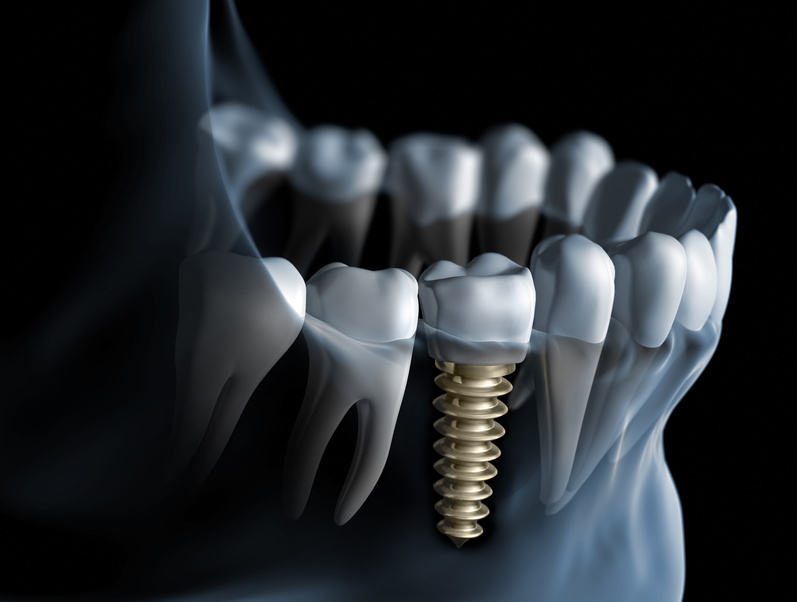

View Larger Image Dental Implantsunrise dentallab2018-09-17T05:56:30+00:00 Project Description Project Details Categories: Implants Share This Post FacebookTwitterLinkedIn Related Projects X-ray Finish